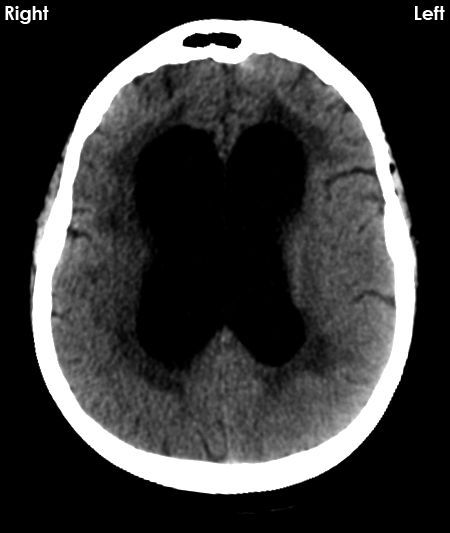

@RadMasterclass

CT BRAIN 24: Patient intubated following prolonged cardiopulmonary resuscitation. What are the abnormalities? Answer https://t.co/SzWQa19oUw